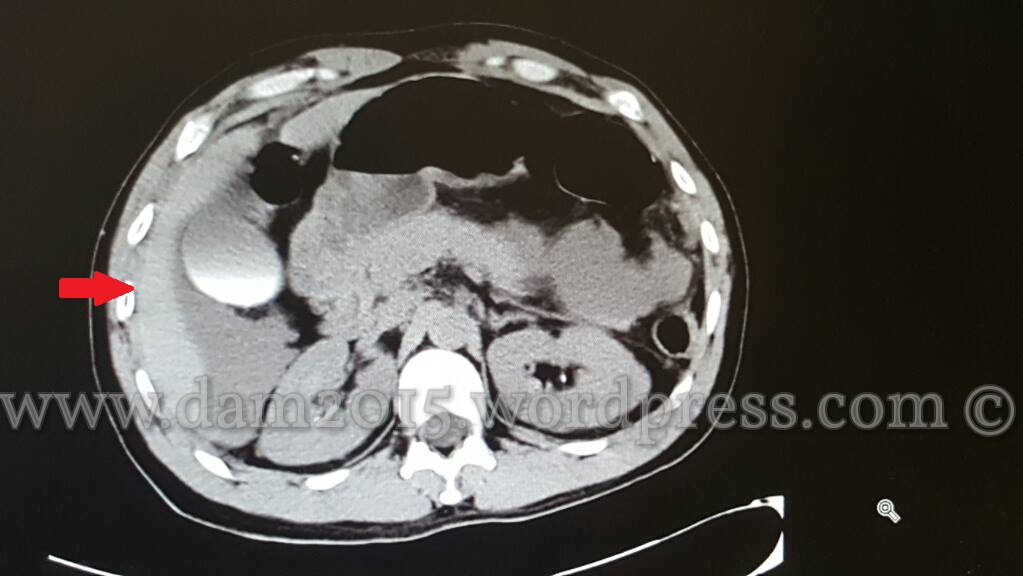

Paziente uomo, 35 anni, con ferita penetrante da arma bianca in fianco sinistro.

Addome acuto, emoperitoneo, aria libera endoperitoneale.

Ferita da punta e taglio di ansa digiunale.

Quota di versamento periepatico.